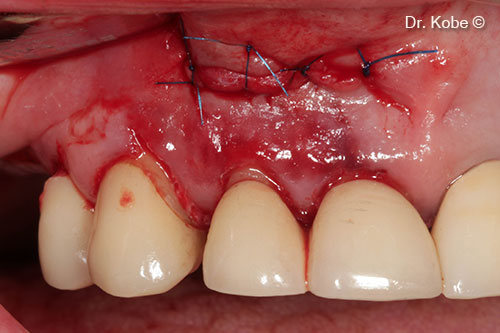

Defect filled with Gel 40

Wound sutured with interrupted sutures